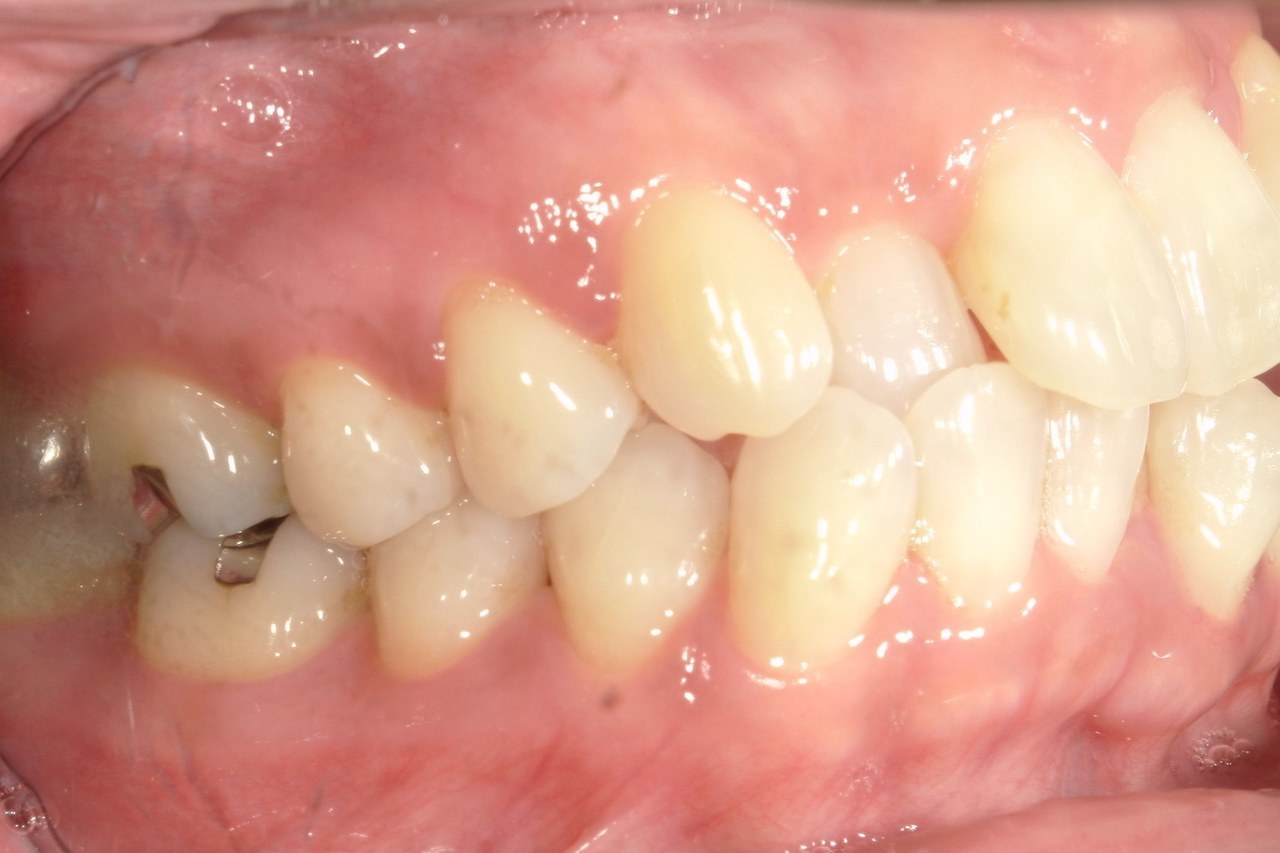

Before

浜松市中央区・自動車学校前駅のインビザラインの症例

Y.S. 30代男性

全体的にガタガタしているのが気になるという主訴だったため、上下左右第一小臼歯を抜歯し、叢生を並べました。

治療の期間:R3. 9/1〜R5. 10/31

治療の価格:88万円